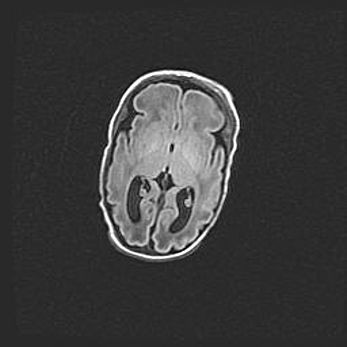

Лейкомаляция с кистозно-глиозной дегенерацией головного мозга.

Возраст: 2 месяца 25 дней

Вес: 6400 г

Окружность головы: 40 см

Срок гестации: 41 неделя

Лейкомаляцию относят к ишемически-гипоксическим повреждениям головного мозга, диагностируемым у новорожденных. При лейкомаляции в головном мозге обнаруживают очаги некроза, возникшие после тяжелой гипоксии и нарушения кровотока. В процессе морфогенеза очаги проходят три стадии: 1) развития некроза, 2) резорбции и 3) формирования глиозного рубца или кисты. Перивентрикулярная лейкомаляция (ПЛ) встречается примерно в 12% случаев среди новорожденных, обычно – у недоношенных детей, причем, частота ее зависит от массы, с которой младенец появился на свет. Наибольшее число малышей страдает лейкомаляцией, если масса при рождении 1500-2500 г.